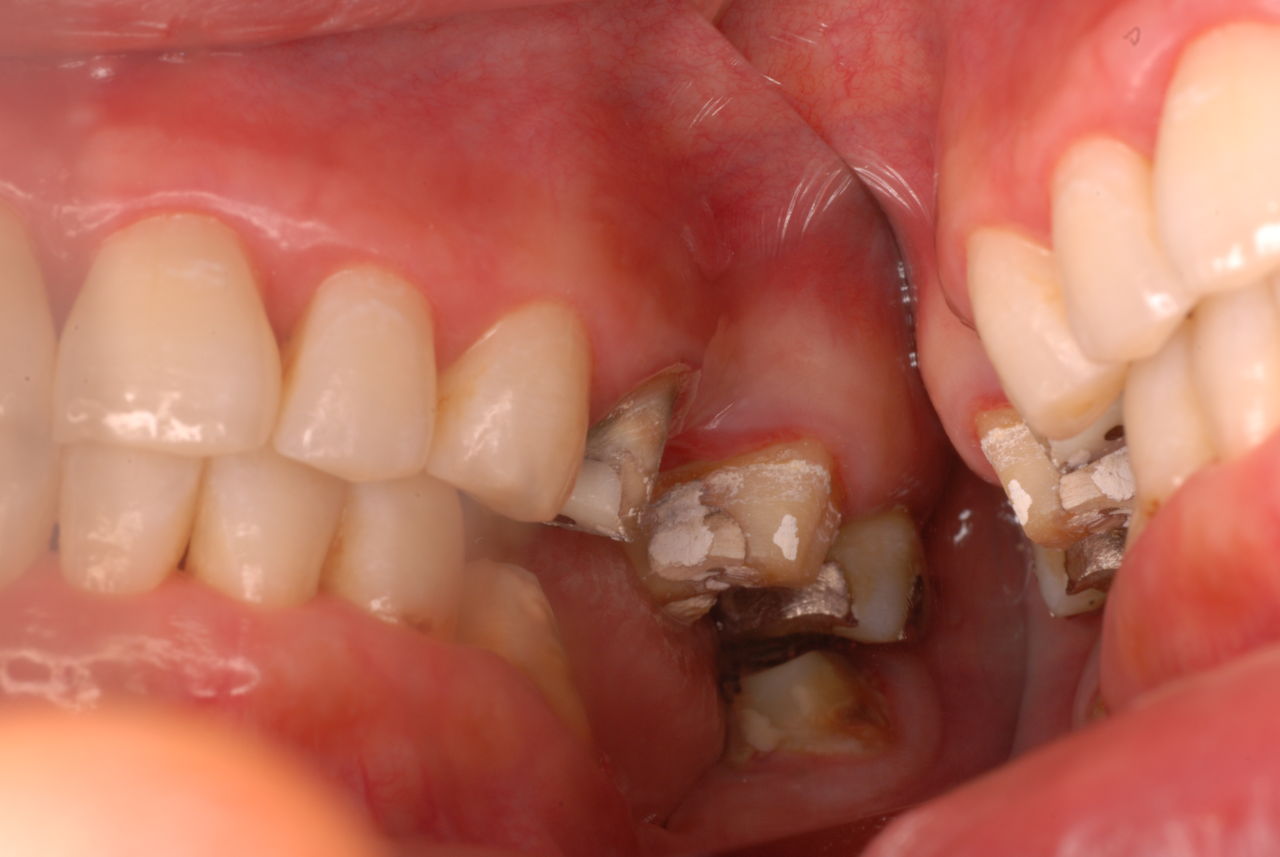

お口の中から差し歯、入れ歯、詰め物を追放しましょう!

口の中の病気を治し、病気を興さない医療を目指します。

二度とお口の中へ変なものを入れなくても済むように

予防に精進いたしましょう!安全な矯正、美容を目指しましょう!